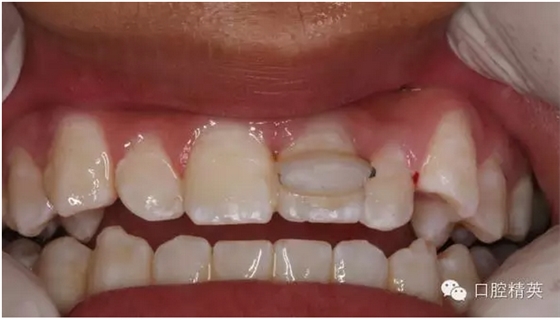

圖17.正確復(fù)位21.臨時光固化粘結(jié)

圖18.復(fù)位臨時固定后的x線根尖片?;颊哐栏c牙槽窩吻合。

圖19.經(jīng)過x線檢查,21復(fù)位和牙槽窩吻合,行13到23粘結(jié)部位的牙面全酸蝕。